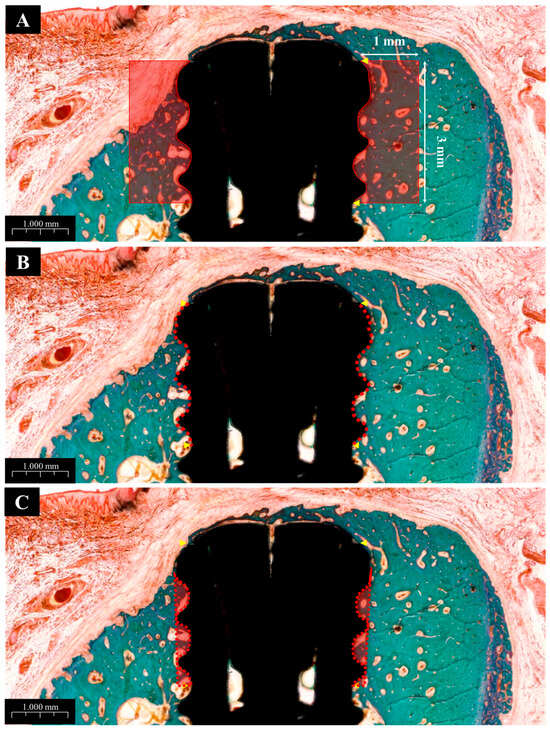

2.2.6. Histological Analysis

3.2.5. Histological Findings

3.2.6. Histometric Findings

| Contents | Groups | Mean ± SD | p-Value |

|---|---|---|---|

| NBA (%) | NS | 43.79 ± 10.60 a | 0.000 * |

| BS | 70.46 ± 5.17 b,c | ||

| PS | 61.76 ± 6.59 b | ||

| PB | 72.75 ± 9.36 c | ||

| BIC (%) | NS | 60.24 ± 3.51 a | 0.000 * |

| BS | 68.81 ± 6.40 b,e | ||

| PS | 70.98 ± 6.63 c,e | ||

| PB | 83.91 ± 3.01 d | ||

| ITBD (%) | NS | 42.86 ± 10.44 a | 0.000 * |

| BS | 63.47 ± 6.03 b,e | ||

| PS | 64.81 ± 7.32 c,e | ||

| PB | 81.32 ± 6.62 d |